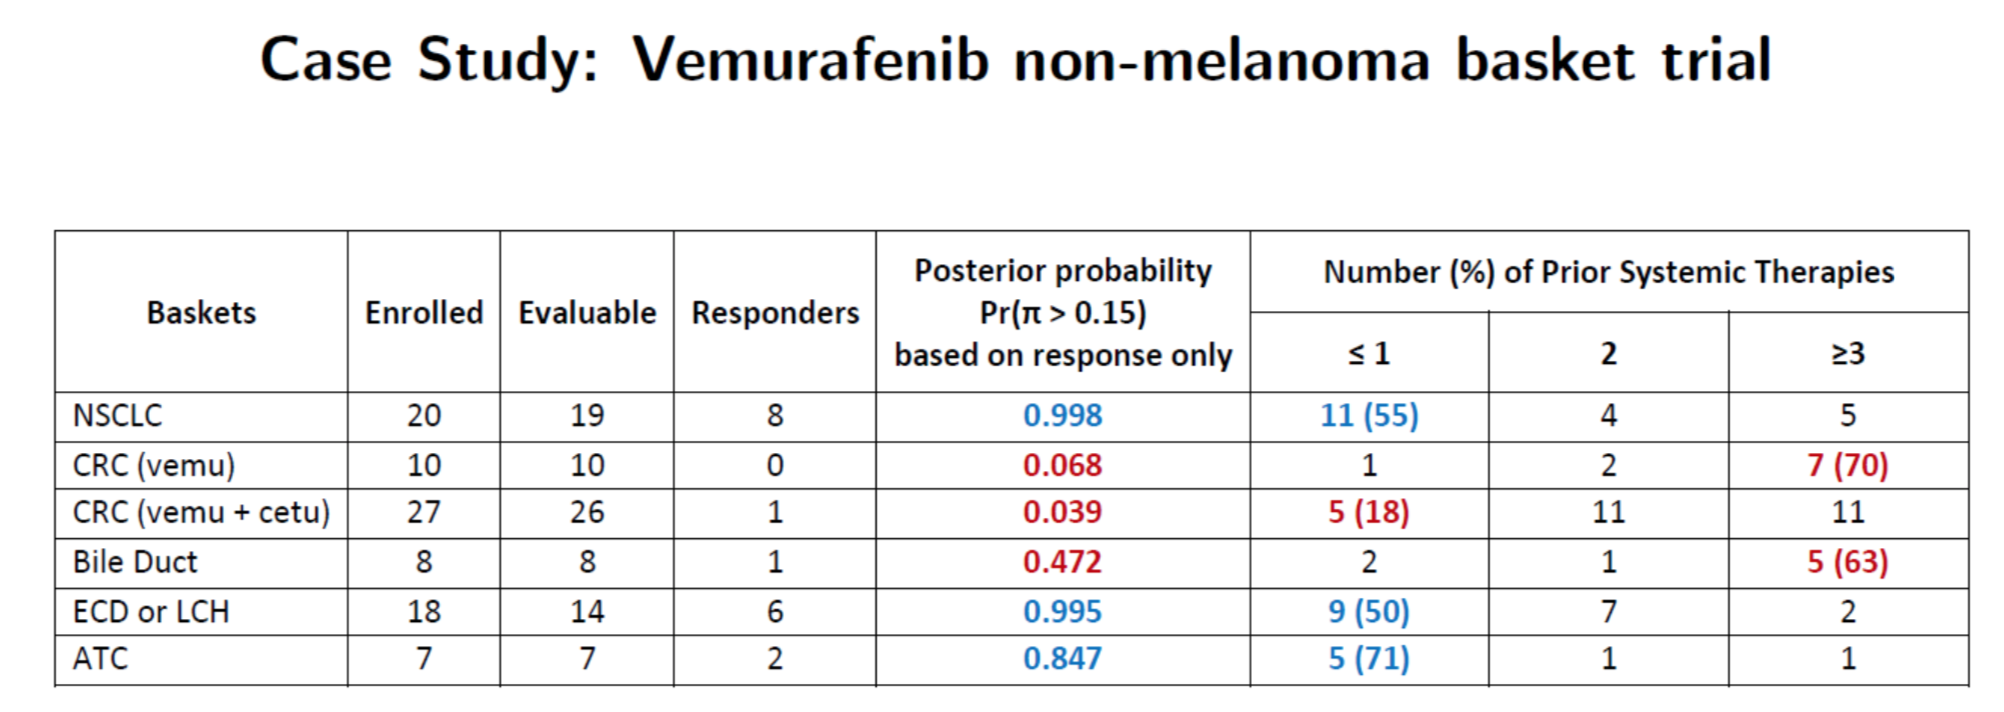

Hobbs, Kane, Hong, and Landin. Statistical challenges posed by basket trials: sensitivity analysis of the Vemurafinib study. Accepted to the Annals of Oncology.